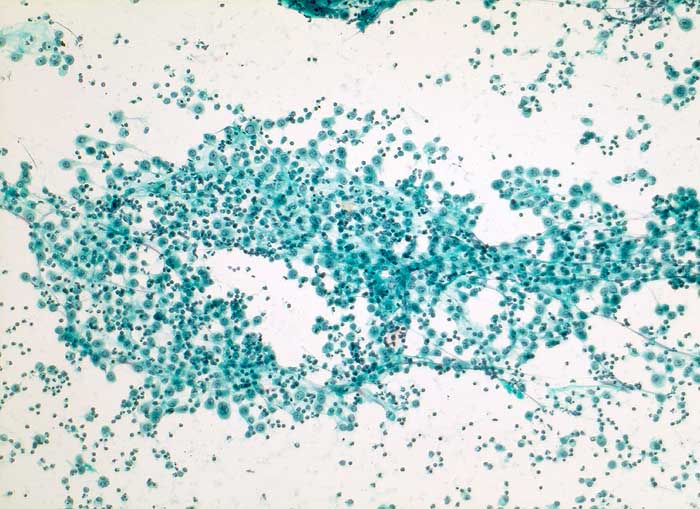

Aszites: Flächenhafte lockere Verbände grossleibiger aktivierter Mesothelzellen und zahlreiche Entzündungszellen.

Dieses immunhistochemische Markerprofil, insbesondere die deutliche Positivität für den Mesothel-Marker Calretinin und fehlende Expression des Epithelmarkers Ber-EP4, passen am ehesten zu Zellen mesothelialen Ursprungs. Auch Zytokeratin 7 wird in normalen Mesothelien typischerweise exprimiert. Insgesamt sprechen die Befunde für ausgeprägte reaktive Veränderungen und gegen ein Karzinom. Insbesondere bei Leberzirrhose werden gelegentlich schwere reaktive Mesothelveränderungen im Aszites beobachtet, die zytologisch ein Karzinom vortäuschen können.